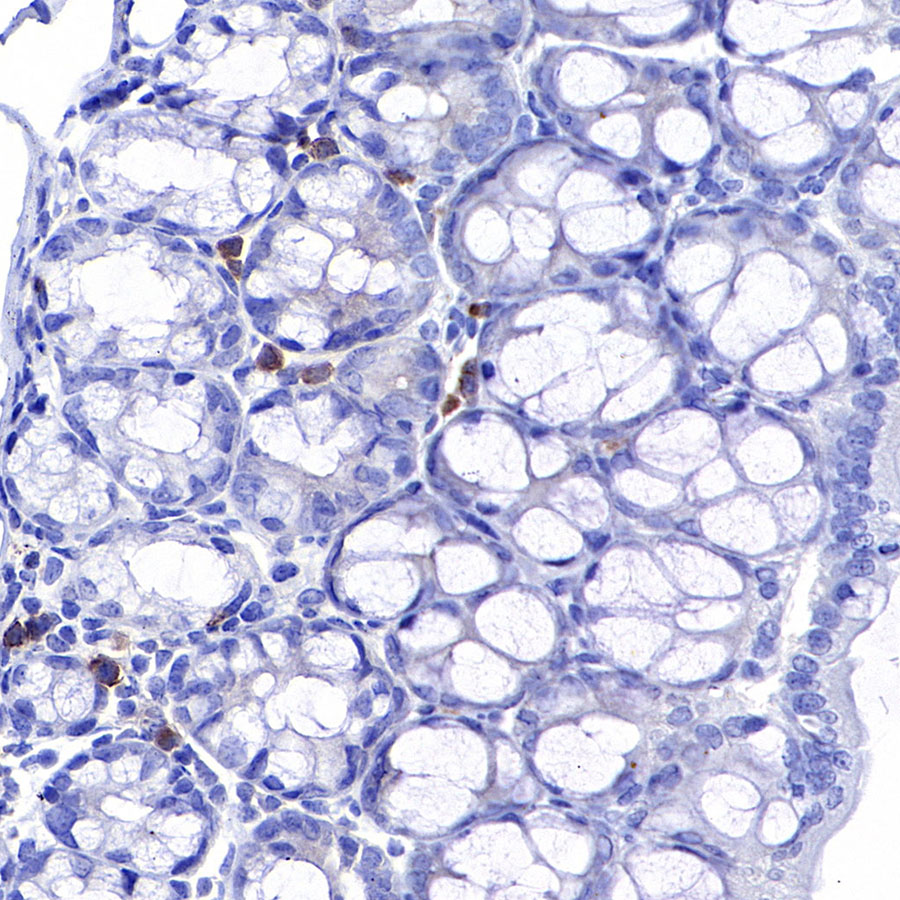

Immunohistochemistry

IHC shows positive staining in paraffin-embedded mouse spleen. Anti-CD8α antibody was used at 1/500 dilution, followed by a HRP Polymer for Mouse & Rabbit IgG (ready to use). Counterstained with hematoxylin. Heat mediated antigen retrieval with Tris/EDTA buffer pH9.0 was performed before commencing with IHC staining protocol.